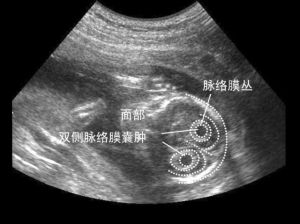

檢出脈絡叢囊腫時應結合其他臨床資料,進一步行羊膜腔穿刺羊水細胞培養或臍帶穿刺取臍血培養,以除外18-三體、21-三體等染色體異常。正常的胎兒也可以出現脈絡叢囊腫,但大多26周后消退。正常的胎兒也可以出現脈絡叢囊腫,但大多26周后消退。如果26周后還不消退,而且是雙側的,孩子生後應該做顱腦的檢查及臍血細胞的染色體檢查。診斷

1.脈絡叢強回聲內見囊性暗區,囊壁薄邊緣光滑,整齊,多呈圓形。囊腫可單發,也可多發。2.動態觀察囊腫大小,如果囊腫小於1cm或越來越小,染色體異常可能性小,同時應注意檢查其他部位是否有新發現的畸形,有時超聲檢出脈絡叢囊腫後,其他畸形還不能檢出。但也有學者認為,脈絡叢囊腫大小、數目、雙側或單側、是否進行性縮小或消失,胎兒患染色體異常的危險度不會改變,檢出脈絡叢囊腫時,應結合其他臨床資料進一步行羊膜腔穿刺行羊水細胞或臍帶穿刺血培養,以除外18-三體、21-三體等染色體異常。